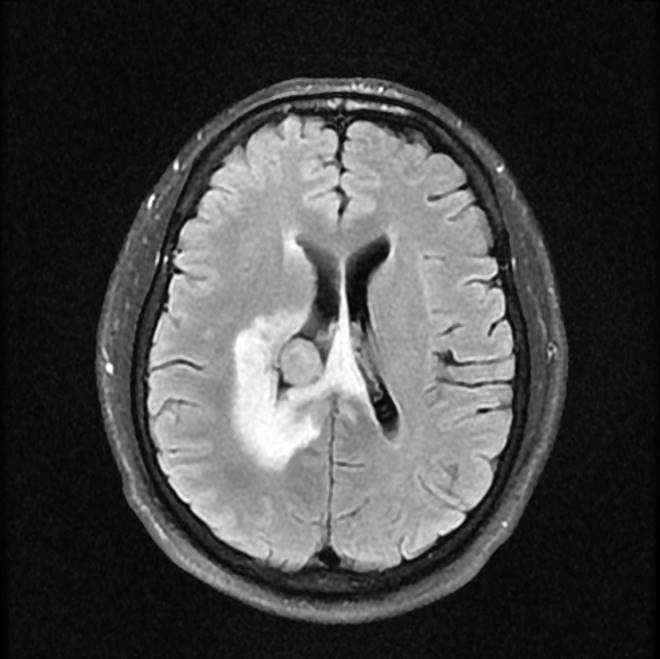

磁共振影像圖

圖1

圖2

圖3

圖4

MR診斷:右側(cè)側(cè)腦室三角區(qū)及側(cè)腦室旁占位,考慮惡性腫瘤可能,間變型腦膜瘤?轉(zhuǎn)移瘤?

MR鑒別診斷

常規(guī)MR檢查是診斷腦膜瘤的有效手段,可以明確腫瘤發(fā)生的部位、形態(tài)和數(shù)目等特征以及病變向鄰近腦實(shí)質(zhì)侵犯的程度和范圍,典型腦膜瘤呈等或(和)稍長(zhǎng)T1、等或(和)稍長(zhǎng)T2信號(hào),??娠@示完整的包膜,增強(qiáng)掃描因腫瘤內(nèi)部新生血管通透性不同呈不同程度強(qiáng)化,由于腫瘤組織的強(qiáng)化程度與腫瘤的惡性程度不完全一致,導(dǎo)致MR常規(guī)檢查在腦膜瘤分級(jí)分型方面仍存在一定的困難。擴(kuò)散加權(quán)成像( diffusion weighted imaging,DWI) 及表觀擴(kuò)散系數(shù)( apparent diffusion coefficient,ADC) 被廣泛用于腦腫瘤的分級(jí)、分子分型和腫瘤侵襲性預(yù)測(cè),并取得了良好的性能。目前,對(duì)于非典型腦膜瘤腦實(shí)質(zhì)侵犯的診斷的金標(biāo)準(zhǔn)依賴于組織病理學(xué)。